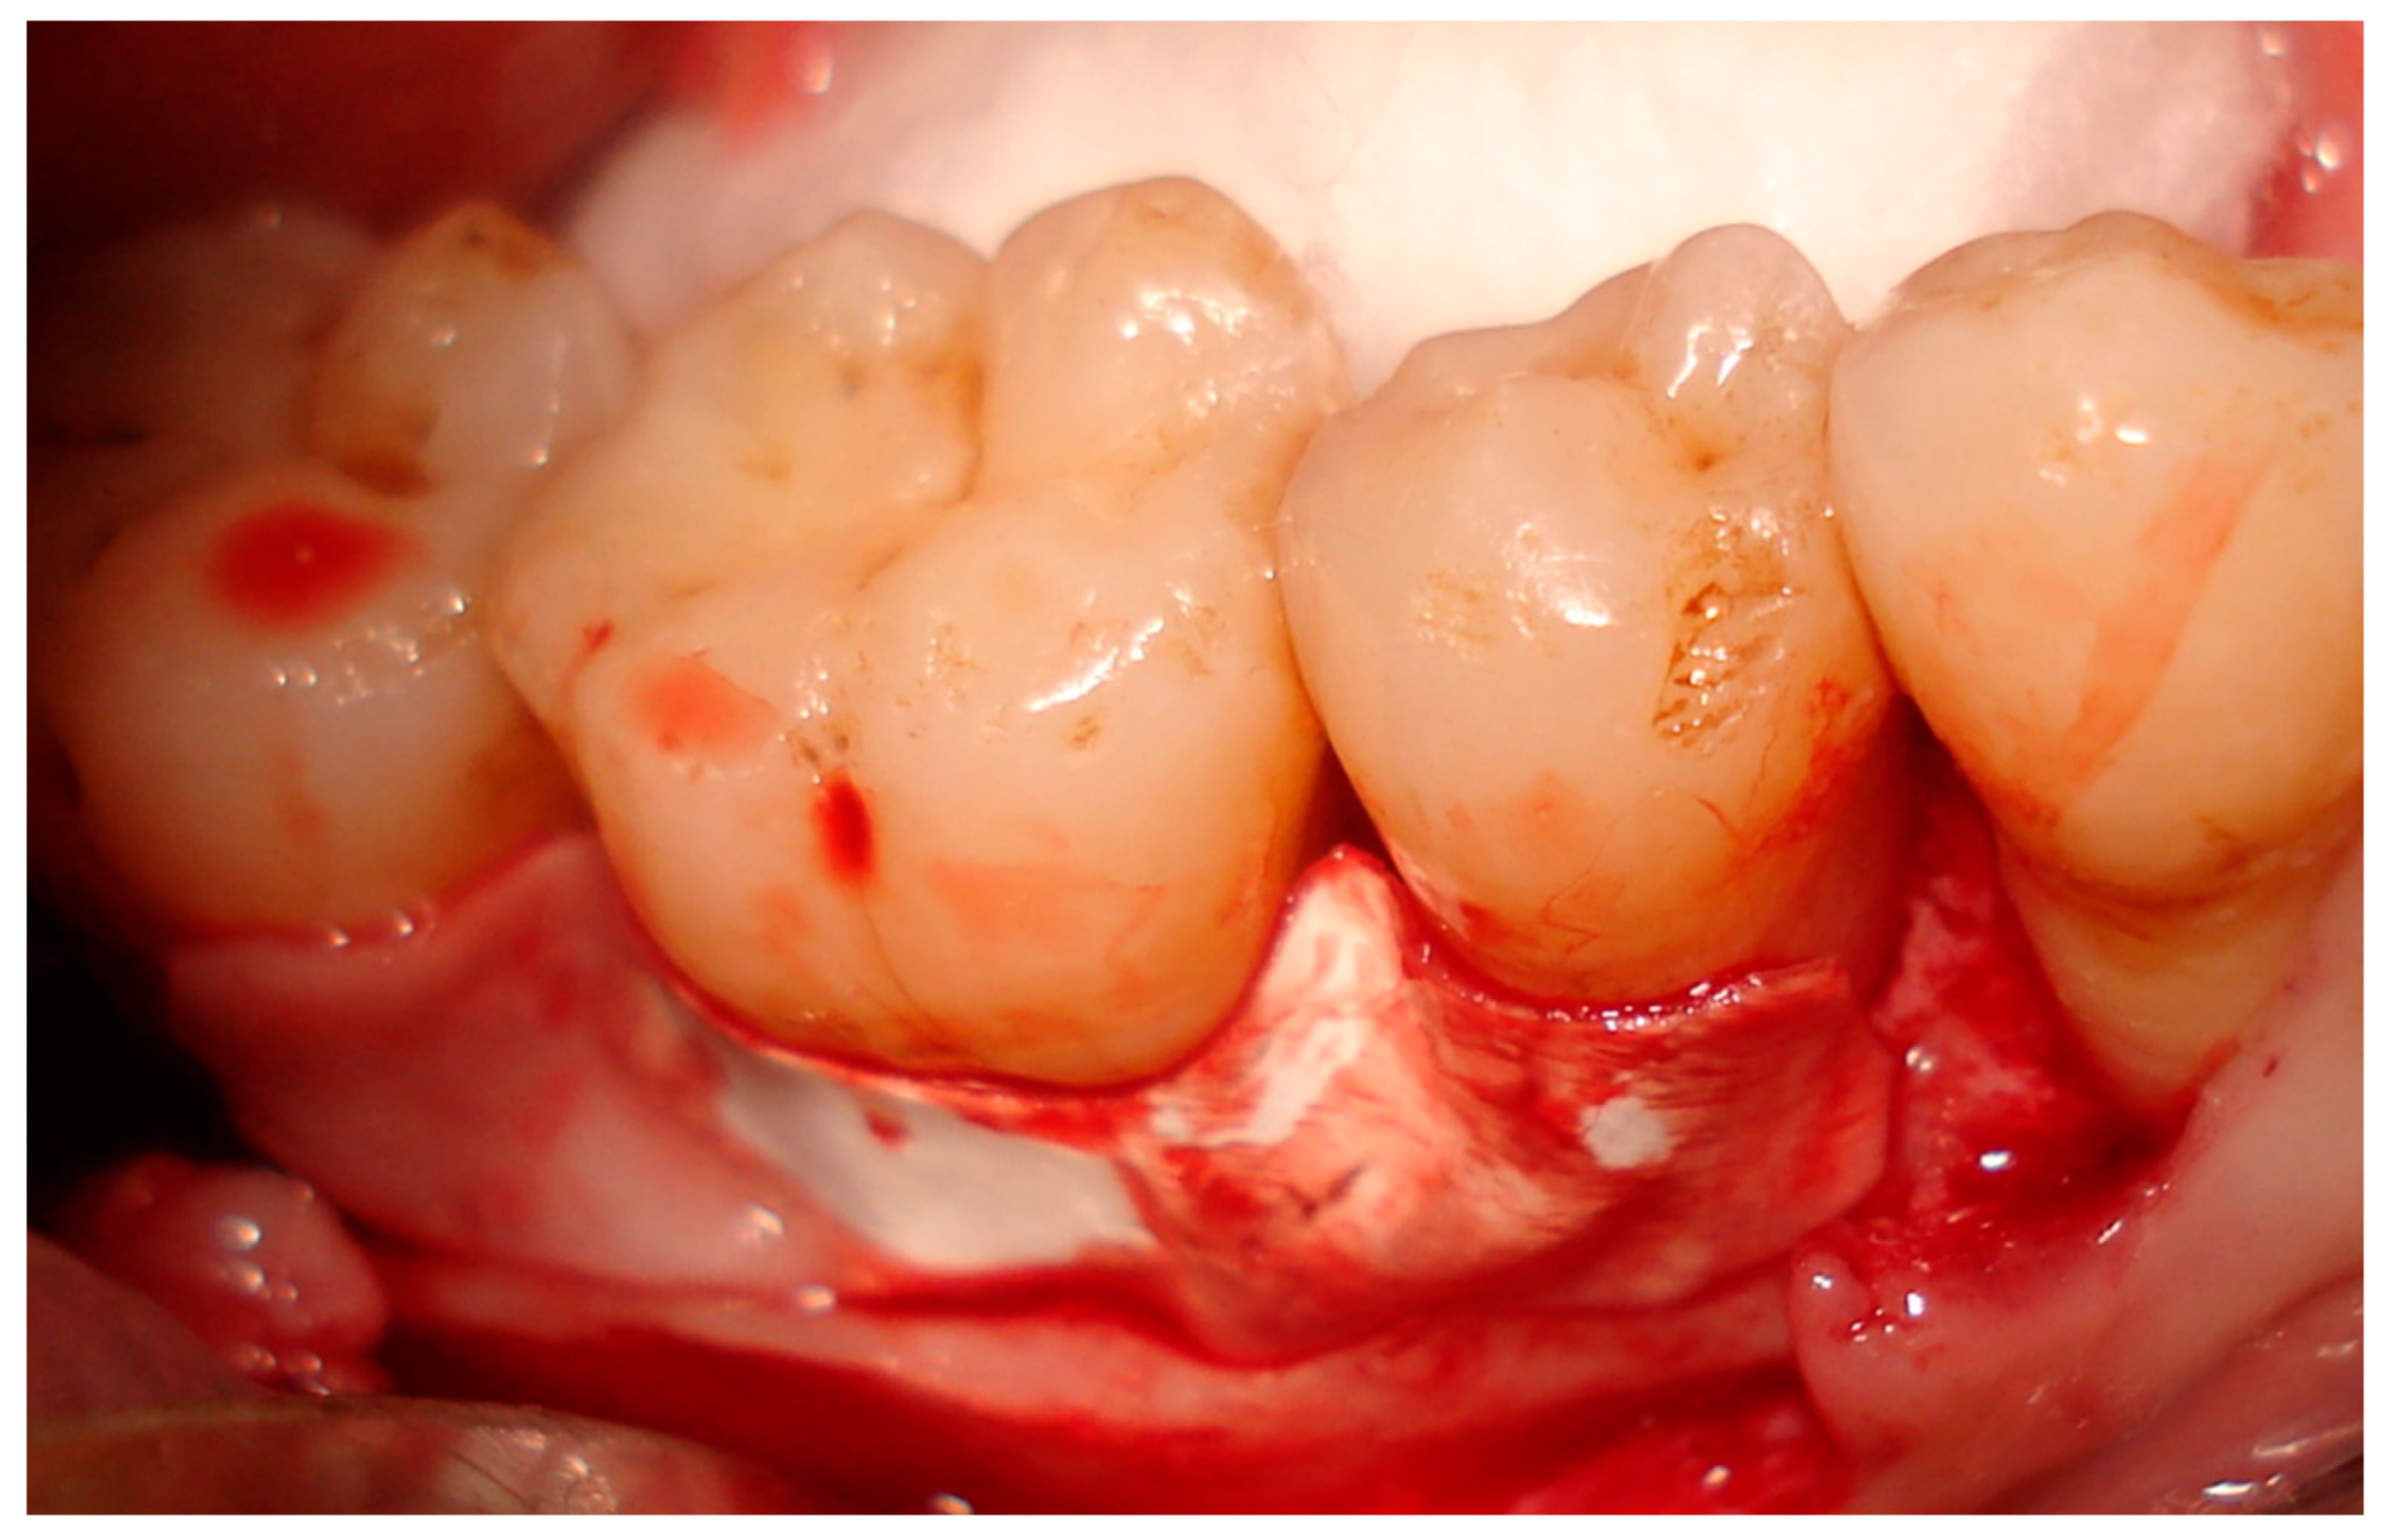

- The surgical site was anaesthetized using the infiltration technique. Full-thickness intrasulcular incisions were carried out around the tooth to be treated, extended by one tooth mesial and one tooth distal, so far as possible according to condition.

- Complete debridement and degranulation of the defect was carried out, with additional scaling and root planning of defects.

- The granulation tissue on the inner side of the flap was curetted. Surgical areas were carefully rinsed with sterile saline, and isolated with cotton rolls.

- In group I patients, the pericardium membrane with nanohydroxyapatite particles on its surface was used alone without bone graft filler. The membrane was trimmed and adapted to cover the furcation defect and was extended from the cementoenamel junction (CEJ) to 3 mm beyond the defected furcation (Figure 2).

- In group II patients, the defects were filled with nanohydroxyapatite bone graft material, and the pericardium membrane was then adapted over the graft, extending from the CEJ to 3 mm beyond the defect.

- Flaps were sutured coronally to the original levels to cover the treated sites with soft tissue using 4-0 vicryl sutures. Simple interrupted sutures were used for flap closure.